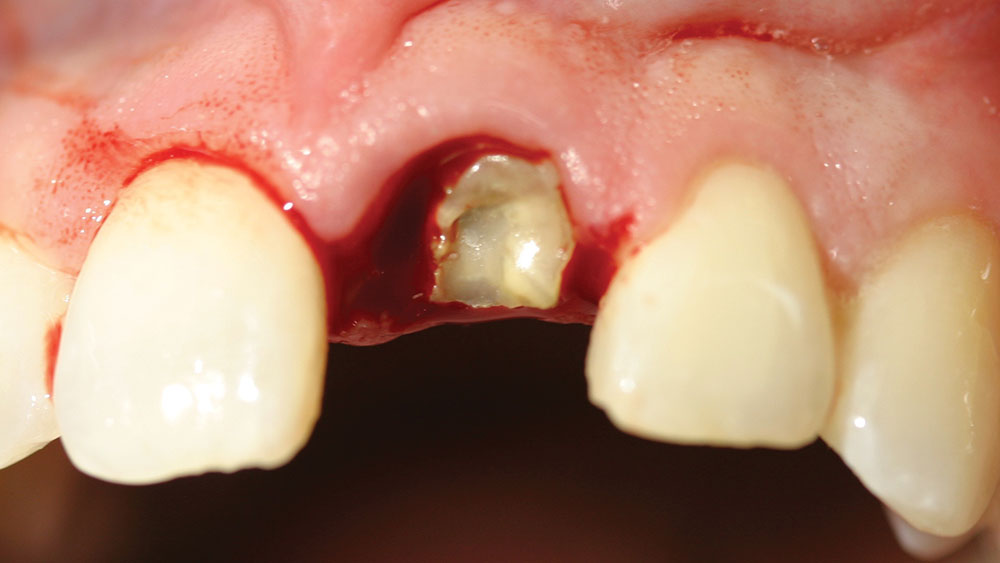

cm1401-rd-corner-efficacy-hahn-tapered-system-1a

cm1401-rd-corner-efficacy-hahn-tapered-system-1b

Figures 1a, 1b: Calibration of the bone loss measurements was determined by measuring the length of the implant (1a), or by measuring the diameter in cases where the implant apex was not visible (1b).